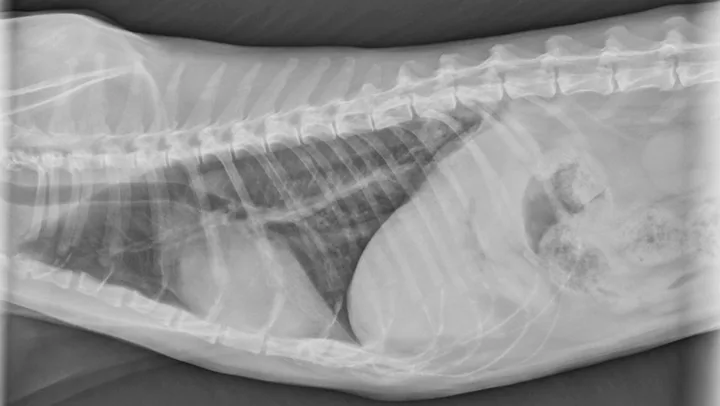

Figure 2

Dorsoventral radiograph of right-sided caudal primary lung tumor. Image courtesy of Rachel Moon, DVM, DACVR

Reported primary lung tumors (Figures 1 and 2) include squamous cell carcinoma and sarcoma, but adenocarcinomas are reportedly the most common histopathologic diagnosis.2 Adenocarcinomas are subcharacterized by location (ie, bronchial, bronchioloalveolar, alveolar) and grade. Carcinomas are graded on histopathology as differentiated or undifferentiated, with the grade directly correlating with metastatic incidence.1,3 Although most primary carcinomas are localized and solitary at diagnosis,1,4 the literature suggests that >50% of undifferentiated carcinomas and 90% of squamous cell carcinomas metastasize,1,3 with one study reporting ≈75% of feline lung tumors as metastatic.4 Metastasis to the lungs, skin, CNS, and digits may occur transpleurally, hematogenously, or via lymphatics or airways.1,3,4

Radiographs may reveal extensive osteolysis of the distal phalanx that may cross the joint space. Thoracic radiographs often show a single primary lung mass, although diffuse nodular disease has also been noted.1 No clinical signs of respiratory distress in affected cats have been reported.6